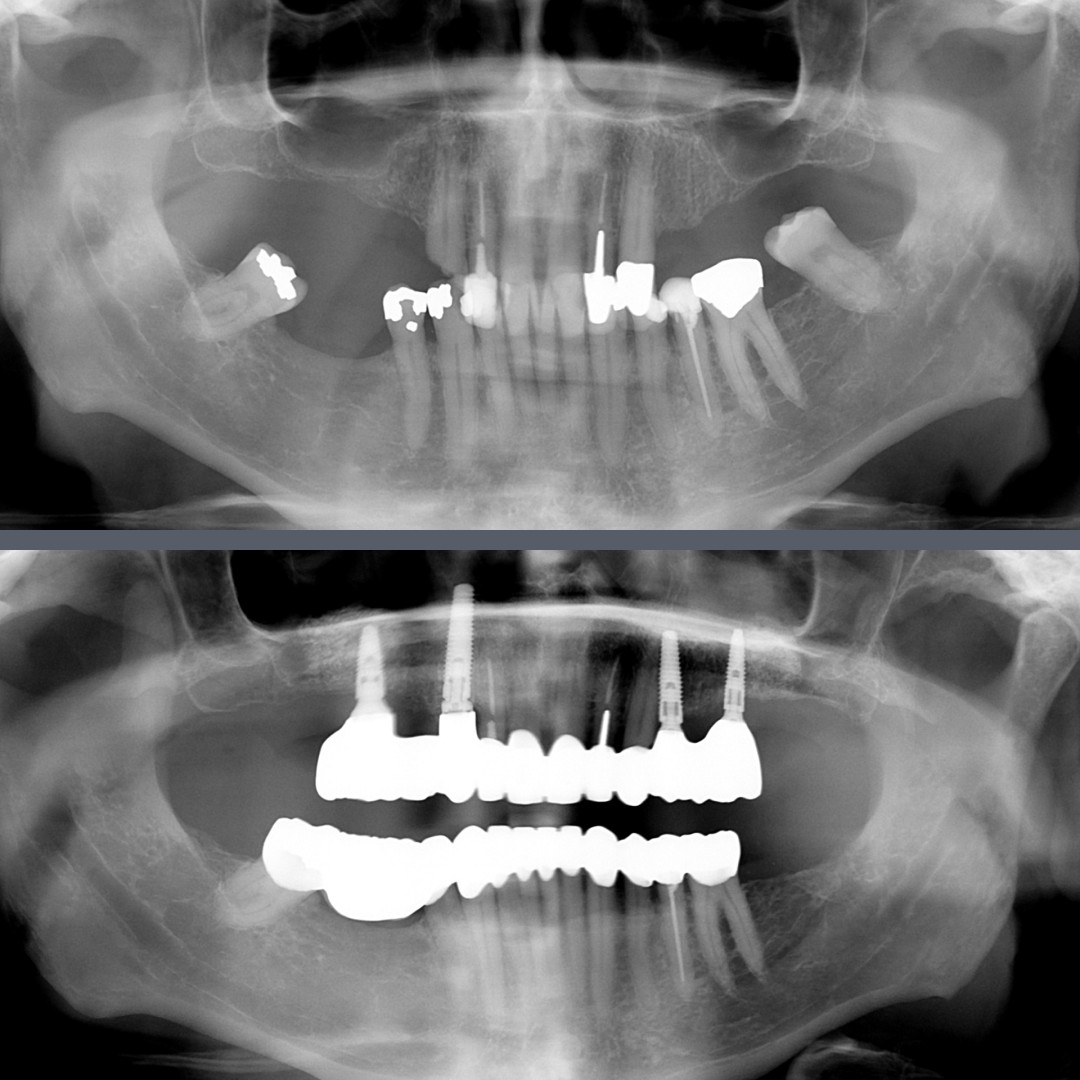

Missing Teeth and Aesthetic Problems – Full Dental Rehabilitation with Implants and Zirconia Bridges

Our Norwegian male patient presented with multiple missing teeth. His remaining teeth, especially those at the front, were also in poor condition. These serious dental issues significantly affected the overall quality of his life.

Due to financial constraints, the patient opted for a partial implant solution. We placed two implants on each side of the upper jaw, and, after the healing period, we attached bridges to the implants to replace the missing teeth. We also replaced the removed front teeth with a bridge. On the lower jaw, after extracting the remaining unsalvageable teeth and allowing the gums to heal, we fitted a full-arch zirconia bridge. The patient wore temporary prosthetics until the final restorations could be fitted.

After completing treatment in seven months and only two trips to Budapest, our patient now enjoys a fully functional and natural-looking set of teeth. This dental rehabilitation has significantly improved his confidence, self-esteem, and overall mood.